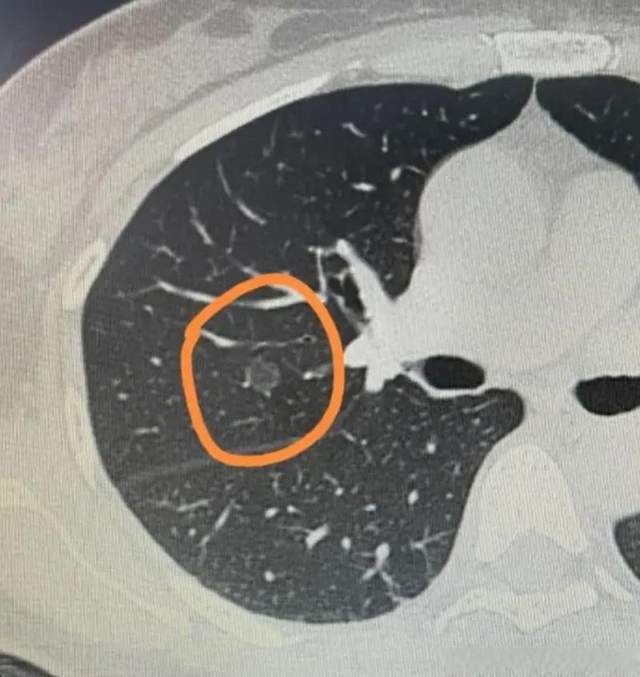

3. “伴有气道壁破坏”:这是最致命的一点。多个肺泡之间的壁破裂,融合成一个巨大的无效空腔(肺大疱),失去了气体交换的功能。

关键后果: 当肺泡被破坏,吸入的氧气难以进入血液,身体里的二氧化碳也难以排出。于是,患者就陷入了 “吸气吸不进,呼气呼不出” 的窒息困局。